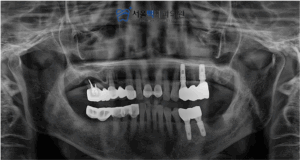

위 어금니의 자리의 임플란트 식립은

‘상악동’이라는 빈 공간이 뚫리지 않게

식립하는 것이 매우 중요하고 어려운데요.

가양역치과, 서울맥치과는

철저한 해부학적 분석과 실력으로

안정적으로 임플란트 식립을 마무리해드리고,

CT를 통해 3차원 사진으로 환자분께 수술 후 상태를 설명드렸습니다.

이전에 보철물과 치아를 발치하고,

성공적으로 임플란트 식립이 되었는데요.